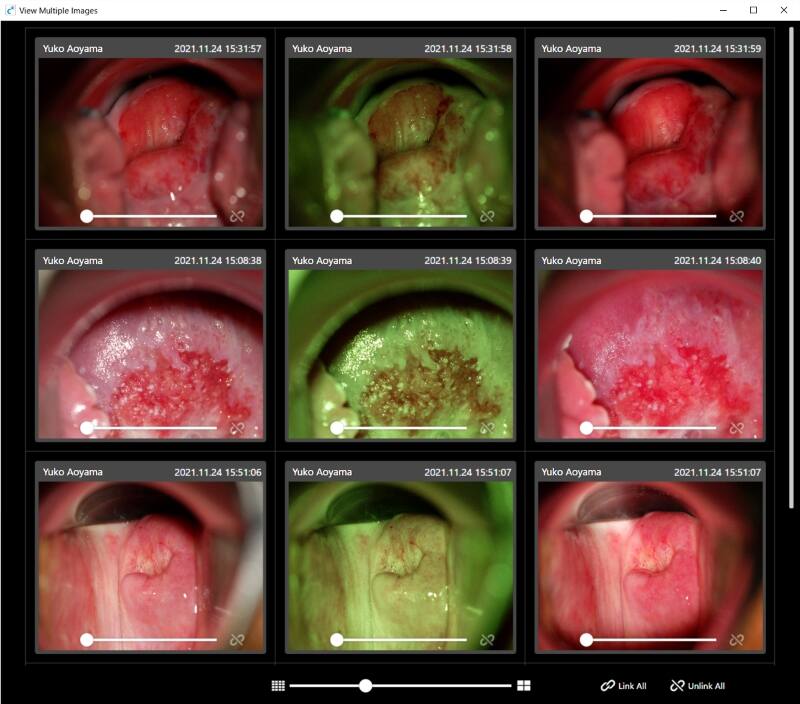

Apresentar várias imagens

Podem ser apresentadas várias imagens selecionadas no mesmo ecrã.

As mesmas lesões podem ser comparadas por ordem cronológica ou lesões semelhantes podem ser visualizadas e comparadas lado a lado.